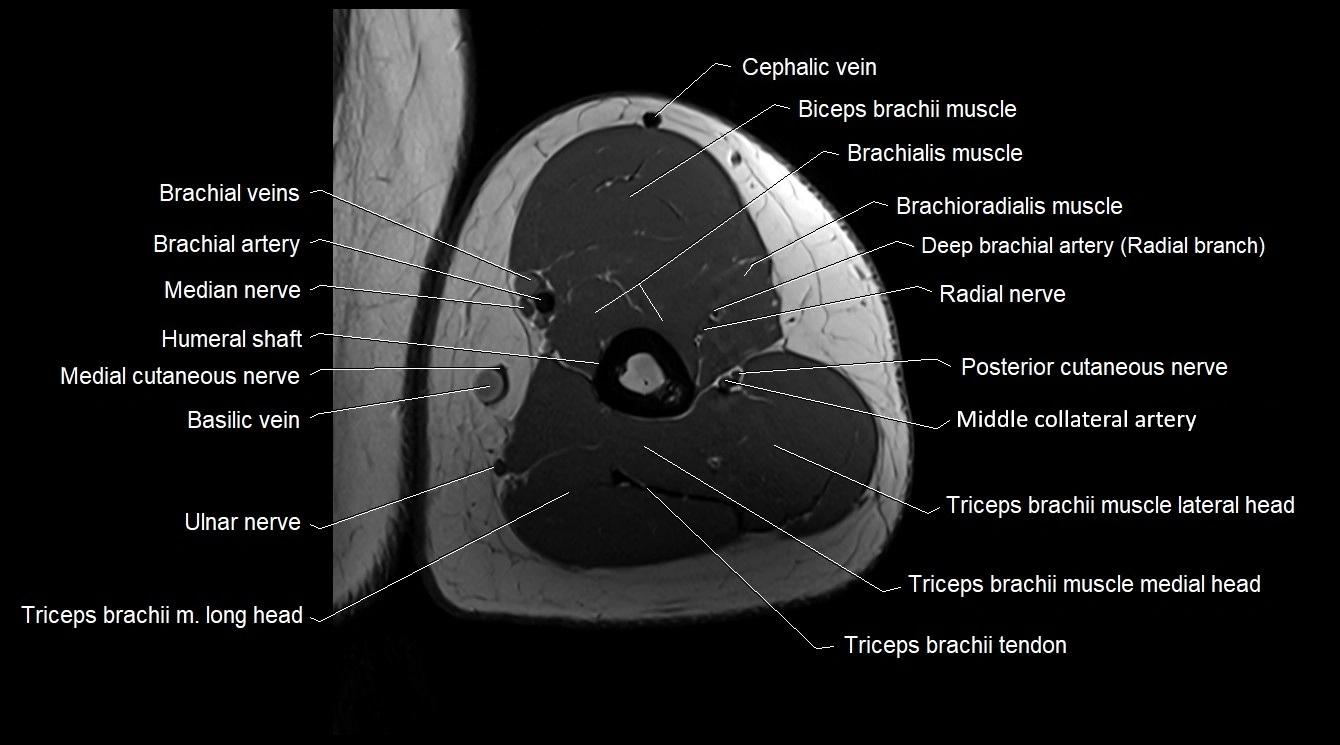

- Biceps brachii muscle

- Brachial artery

- Brachialis muscle

- Brachioradialis muscle

- Cephalic vein

- Lateral head of triceps brachii muscle

- Lateral intermuscular septum

- Long head of triceps brachii muscle

- Medial head of triceps brachii muscle

- Median nerve

- Middle collateral artery

- Radial nerve

- Triceps brachii muscle

- Triceps brachii tendon